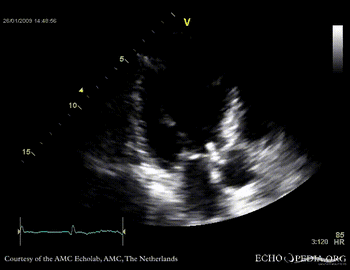

Aortic valve endocarditis with vegetation

Case description: This patient had endocarditis with an aortic valve vegetation

E00114.gif E00115.gif

PLAX showing an aortic valve vegetation PLAX Excentric aortic valve regurgitation